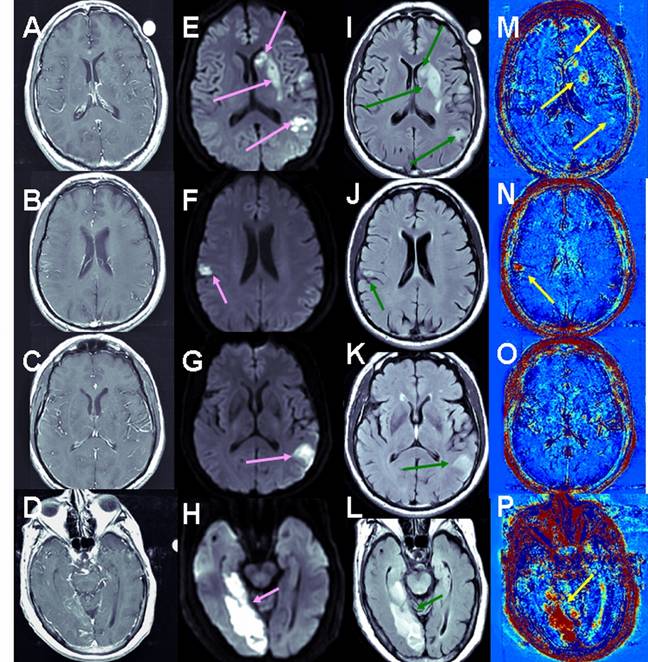

Stroke Cohort Results: Unlike brain metastases in which part of the enhancing tumors appear blue (fast clearance of the contrast from the tumor), all the strokes analyzed in this study appeared red in the subtraction maps, suggesting slow contrast accumulation in the tissue. Examples are shown in Figure 4.

Figure 4

Examples of BBB maps in ischemic stroke. Contrast-enhanced T1-MRI (A-D), DWMRI (E-H), T2 FLAIR (I-L) and enhanced maps (M-P) of 3 patients several days after the onset of ischemic strokes. The stressed tissue is enhanced on the DWMRI and FLAIR. BBB opening is depicted in red in the maps. Patient #2 (A, E, I, M) had a large stroke, divided into several ischemic lesions. Moderate BBB opening was depicted in several regions within these lesions. Patient #14 (B, F, J, N, C, G, K, O) had two ischemic regions. The small lesion showed significant BBB opening (N), while the larger lesion showed no evidence of BBB compromise (O). The stroke of patient #12 (D, H, L, P) presented significant BBB opening both in T1-MRI and on the subtraction maps. Still, the volume of BBB opening depicted on the maps was significantly larger than in the T1-MRIs.

Overall, 33 patients were included in the analysis. When calculating the BBB maps using the 2nd time point at 14.4±0.3 min, 12 exhibited no BBB abnormalities (score 0), 9 exhibited BBB opening only in the maps (score 1&2), and 12 exhibited opening in the maps and in T1-MRIs (score 3). Thus 27% of the patients depicted BBB opening that was detectable on the maps but not on T1-MRI. Of the 12 patients with score 3, the volume of BBB opening in the maps was 2.7 times that in T1-MRI: 4.2±1.5 cm3 vs. 1.5±0.6 cm3, p<0.0005 (Wilcoxon matched-pairs signed-ranks test). On maps using the 2nd time point at 7.0±1.7 min, BBB opening was 1.8 times larger (P<0.009) than in the T1-MRIs. The difference between the volumes calculated from the 7 min maps was significantly smaller than that calculated from the 14.4 min maps (p<0.04, paired t test).

The average score of lacunar strokes (n=10) was significantly lower than that of non-lacunar strokes (n=23): 0.5±0.2 vs. 1.9±0.3, p<0.003 (unpaired t test).